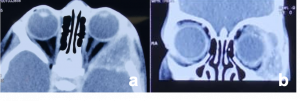

| Pleomorphic Adenoma[38][38] | 40-55 years | Indolent painless enlargement of the gland causing proptosis and characteristic S-shaped ptosis | CT- well circumscribed homogenous mass in lacrimal fossa with bony scalloping.

MRI- bright enhancement. T1- hypo/iso intense T2- hyperintense |

Bone remodelling may be present but no bony erosion. | Pleomorphic Adenoma. a & b). Non-contrast CT scan demonstrates well-defined, round to oval lesions, smooth in outline, associated with prominent scalloped lacrimal fossa (orange curved line) formation due to pressure without bone erosion in comparison to left orbit (orange arrows). Long-standing large tumours lobulations and radiolucent areas of cystic degeneration. |